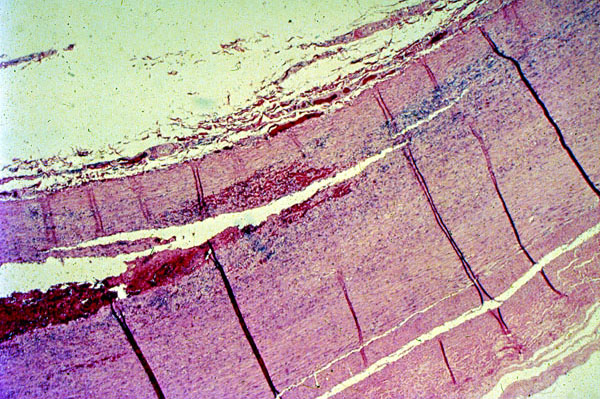

Aorta, Marfan syndrome, dissecting aneurysm

Patient with

Marfan syndrome

. Dissecting

aneurysm

of the aorta. H&E